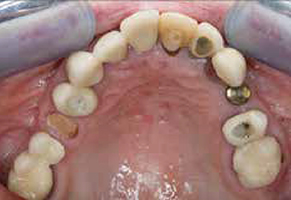

Het implantaat dat geplaatst is in het tweede kwadrant staat volgens de verwijzer niet goed in de boog. Er is geen ruimte om een kroon op dit implantaat te plaatsen zonder de kronen op 23 en 25 te beschadigen (afbeelding 4 ).

Solo-opname 23 en 24